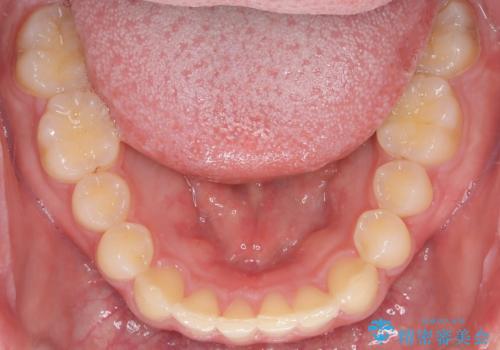

【インビザライン】前歯のガタガタと、前歯の噛み合わせが深いことを治したい。

- 前歯のガタガタと、前歯の噛み合わせが深いことを治したい。との主訴で来院されました。

シミュレーションを用いながら患者様と仕上がりについて相談しインビザラインにて治療を行いました。

仕上げは追加アライナーを数回利用しておこないました。